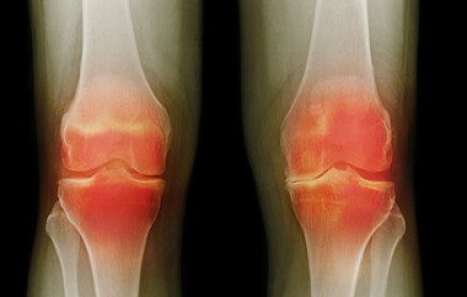

التهابات العظام والمفاصل من أكثر الأمراض الشائعة بين ملايين الأشخاص حول العالم، خاصة كبار السن والسيدات، وهى تعيقهم عن الحركة بأريحية وأداء الأعمال اليومية المخولين بها، ومن جانبه يسلط الدكتور خالد عمارة، أستاذ جراحة العظام بكلية الطب جامعة عين شمس الضوء عليها، لافتا إلى أنها تنقسم إلى ثلاثة أنواع أساسية، تشمل:

3. التهابات نتيجة الاحتكاك المستمر أو الاستعمال والإجهاد غير الطبيعى وينتج عنها خشونة المفاصل والتهابها.

وفيما يتعلق بالالتهابات الناتجة عن الإجهاد والاحتكاك، أوضح أستاذ جراحة العظام أنه يمكن علاجها بالأدوية والعلاج الطبيعى، لكن فى المراحل المتأخرة يكون العلاج بجراحة المنظار والحقن الموضعى أو بجراحات تغيير المفاصل.